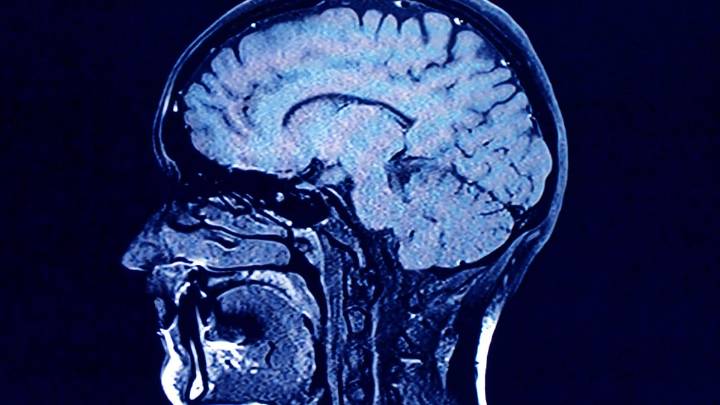

As we age, the human brain rewires itself.

The process happens in distinct phases, or “epochs,” according to new research, as the structure of our neural networks changes and our brains reconfigure how we think and process information.

For the first time, scientists say they’ve identified four distinct turning points between those phases in an average brain: at ages 9, 32, 66 and 83. During each epoch between those years, our brains show markedly different characteristics in brain architecture, they say.

The findings, published Tuesday in the journal Nature Communications , suggest that human cognition does not simply increase with age until a peak, then decline. In fact, the phase from ages 9 to 32 is the only time in life when our neural networks are becoming increasingly efficien